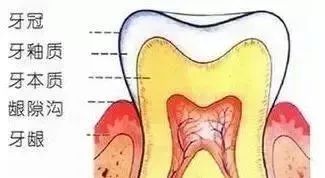

主要是利用过氧化物改变“外套”的半透明度和“内搭”的颜色从而让牙齿变白,适用于轻症患者。分为诊室漂白和家庭漂白,顾名思义,后者是在家里遵医嘱完成的。

主要指需要磨除牙体组织的一种手段,包括渗透树脂、贴面、全冠。区别在于磨除牙体组织量的多少,渗透树脂<贴面<全冠。

渗透树脂适合于轻症的牙齿变色,对于重症者,后两者效果更佳。同时贴面和全冠技术还可以与漂白技术结合,通过漂白先改变牙齿原背景色,修复后效果更佳。